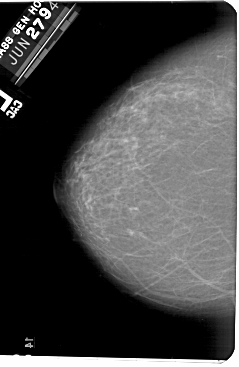

A_1561_1.LEFT_CC

LEFT_CC LINES 5491 PIXELS_PER_LINE 3571 BITS_PER_PIXEL 12 RESOLUTION 43.5 NON_OVERLAY